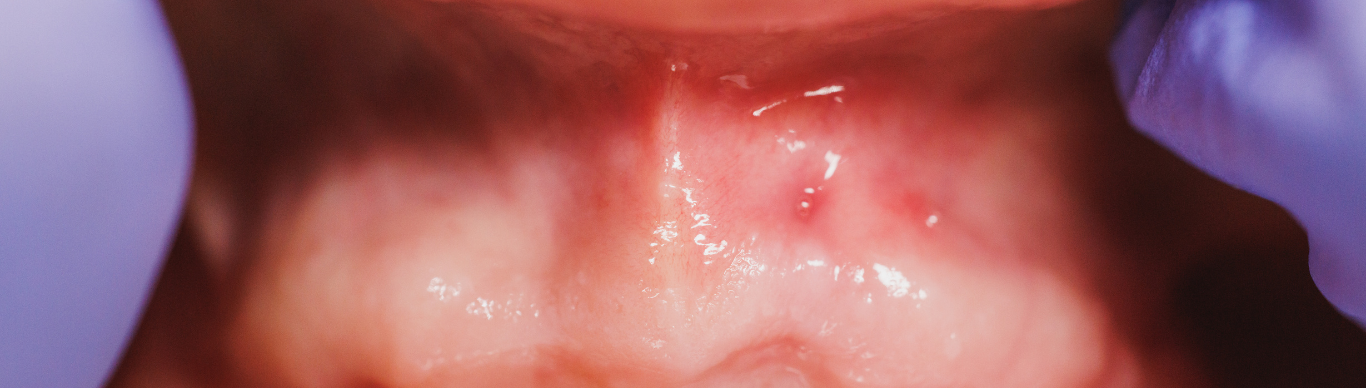

Dr. Whitman described how oral tissues respond directly to fluctuations By Mcdenver Fernandez | February 3, 2026